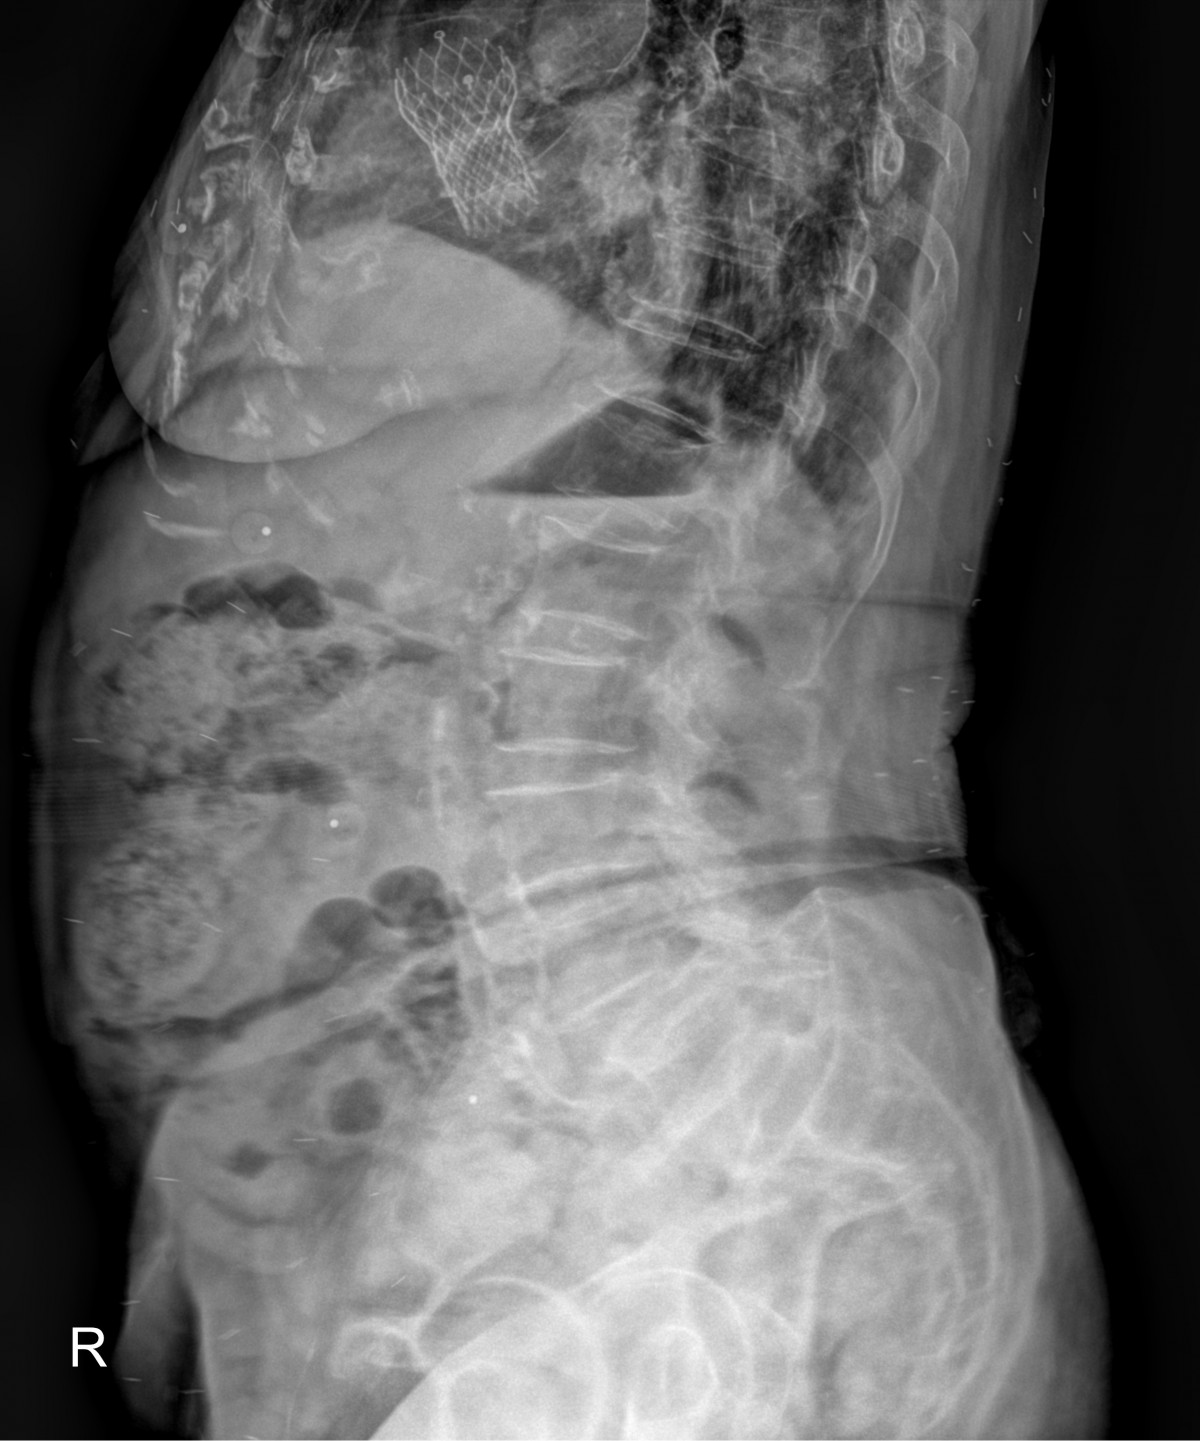

정지영원장님 허리 골절 골시멘트 성형술 김재O 환자

dae765e4d9ac96aee867c9d6292d8784_1758007806_5731.jpg